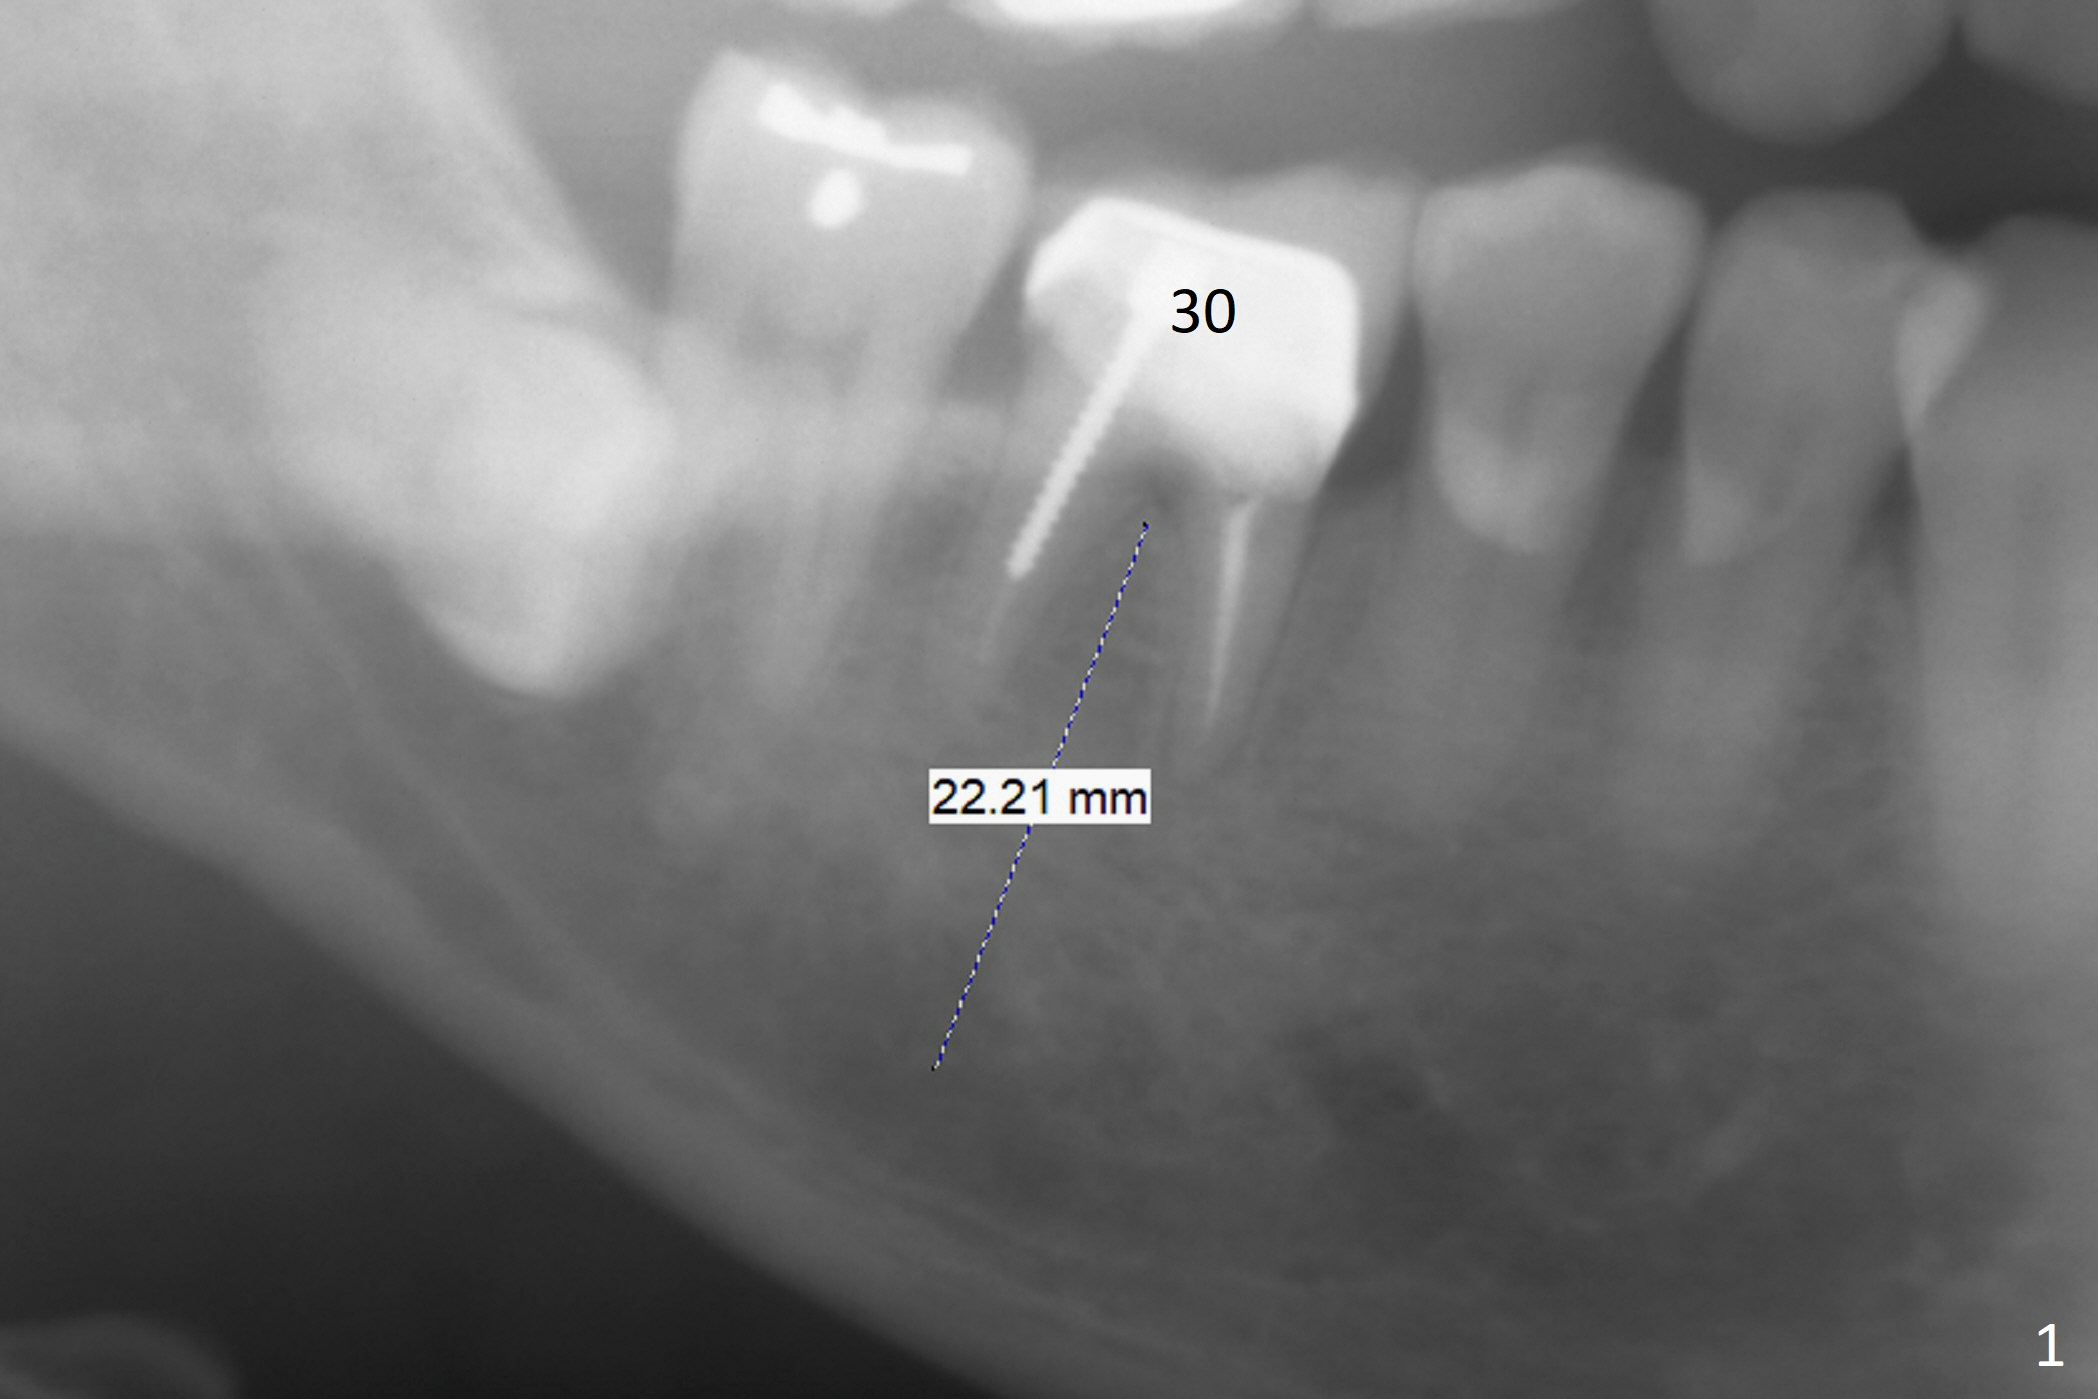

There appears no bone resorption at the septum of the tooth #30 of a 61-year-old man with 22 mm of bone (Fig.1; 10 years ago). The septum starts to have bone loss without symptom 3 years earlier (Fig.2 ^). Now the tooth is symptomatic with bone lesion also involving the mesial apex (Fig.3 *). Osteotomy will be initiated in the flattened septum with 4 mm mesiodistal width. Prior to placing a 13 mm IS implant, the depth of the last 2nd drill will be 15 mm. Prepare Magic Expanders. Place Magic Split blade buccolingually to expand the septum mesiodistally.